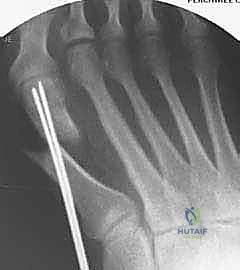

هذه هي اللحظة الحاسمة في العملية. يقوم الدكتور هطيف بإجراء القص العظمي على شكل حرف (V) ممتد. دقة زاوية القص هنا تحدد نجاح العملية بالكامل.

الخطوة الثالثة: القص العظمي الممتد (The Extended Osteotomy)

باستخدام منشار جراحي متذبذب دقيق جداً، يقوم الدكتور هطيف بعمل قطع عظمي على شكل حرف (V). يتميز هذا القطع بأن ذراعه السفلي يمتد طويلاً على طول محور العظم المشطي. يتم توجيه القطع بزوايا ثلاثية الأبعاد محسوبة مسبقاً لتجنب قصر إصبع القدم أو ارتفاعه عن الأرض بعد الجراحة.

إدخال أسلاك التوجيه (K-wires) لتثبيت العظم مؤقتاً والتأكد من الوضعية الصحيحة باستخدام جهاز الأشعة السينية داخل غرفة العمليات (C-arm) قبل وضع المسامير النهائية.